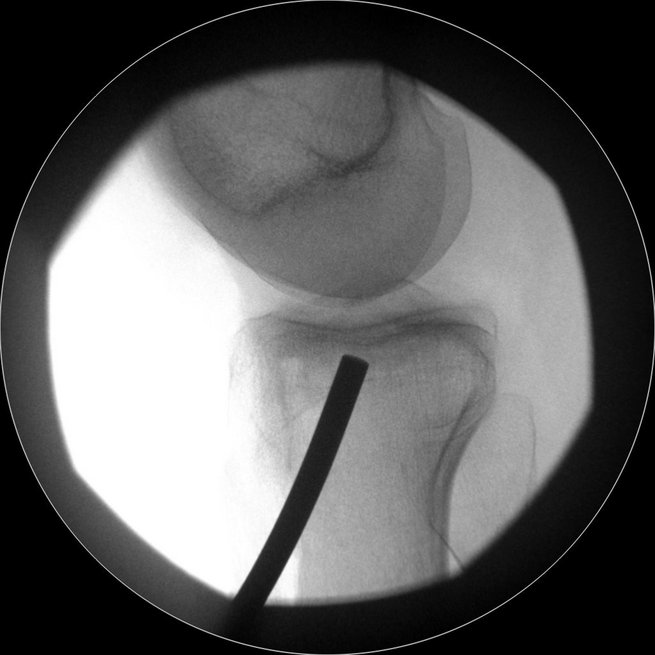

Eine der häufigsten Sportverletzungen im Bereich des Kniegelenkes ist die vordere Kreuzband-Ruptur. Vor allem bei jungen, sportlich aktivem Patienten ist oftmals eine sogenannte VKB-Ersatzplastik notwendig. Goldstandard ist der Ersatz des gerissenen Kreuzbandes durch eine körpereigene Sehne, ggf. können noch stehende Restfasern als Leitstruktur belassen werden. Hierzu stehen verschiedene Transplantate zur Verfügung (Hamstring-Sehnen, Quadrizepssehne, …) die individuell ausgewählt werden. Zusatzverletzungen des Meniskus oder der Seitenbänder werden ebenfalls im Rahmen der Operation behandelt. Das Kreuzband wird über Bohrkanäle an die anatomische Position gebracht und dort mittels sog. Interferrenzschrauben im Kanal verblockt.

Re-Ruptur des vorderen Kreuzbandes

Im Falle von Re-Rupturen des vorderen Kreuzbandes ist in manchen Fällen keine direkte einzeitige Versorgung mit einem neuen Kreuzband möglich, z.B. wenn sich die Bohrkanäle geweitet haben. Dann müssen die alten Kanäle in einem ersten Eingriff gefüllt werden und die erneute Kreuzbandplastik erfolgt nach einigen Monaten. Auch Achs-Fehlstellungen, die das Risiko einer weiteren Ruptur begünstigen würden, werden abgeklärt. Insbesondere eine X-Bein-Stellung oder eine Verkippung des Schienbeinkopfes (sog. „Slope“) gelten hier als Risikofaktoren, die ggf. vor einer erneuten Versorgung mit einem Kreuzband behandelt werden müssen – ebenso wie periphere Instabilitäten, die ebenfalls mit abgeklärt werden müssen.